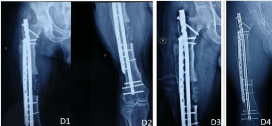

On July 6, 2020, the patient returned to the operating room again to remove all external fixators and bone cement mixed with antibiotics. The blood fluid in the medullary cavity was cultured, the subsequent results indicated that no bacterial growth was observed. Then, 11*380 mm metal interlocking intramedullary nail (A-UFN-02, Xiamen Dabo Technology) was implanted after reaming the proximal and distal femur, the ipsilateral iliac bone was cut into 10*5*5 mm bone strips, mixed with 2. 0g vancomycin, and implanted into the femoral defect, considering the large defect of femur, the metal locking plate (LCLP01-14hole, Xiamen Dabo Technology) was implanted in the lateral femur to play the role of eccentric fixation (Figure 4 D1-2). The patient was given vancomycin intravenously, and rifampicin was given orally one week later, laboratory tests showed that ESR: 64 mm\h, hs-CRP: 27. 61 mg\l, pct-q: 0. 09 ug\l. During the whole treatment, the body temperature fluctuated within the normal range. One month after operation, the X-ray film of femur was reexamined as shown in Figure (Figure 4 D3-4) and the wound healed well (Figure 5 E1-2). Reexamination of inflammatory indicators showed that: ESR: 50 mm\h, hs-CRP: 16. 55 mg\L, pct-q: 0. 07 ug\ L. The patients were very satisfied with the current situation.

Figure 4. D1-2. the X-ray films of femur were reexamined after replacement of internal fixation materials; D3-4. the X-ray films of femur were reexamined after 4 weeks of replacement of internal fixation materials